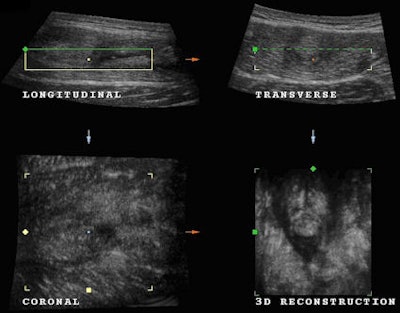

Twenty days after this initial ultrasound examination, the patient presented for a checkup scan. He was feeling much better and no longer suffered from pain. His trainers were keen to get him back to training. Once again, the muscle was examined with both 2D and 3D ultrasound.

A new volume acquisition was obtained and studied to perform a detailed examination of the condition of the muscle and assist in a complete assessment of the patient's condition before putting the muscle under new strain. The volume acquisition obtained demonstrating the condition of the muscle is shown below (Fig. 5 and 6).

Healing of the tear appears as irregular hyperechoic tissue located distal to the severed muscle due to local scarring tissue. Volume loss and fatty infiltration of the injured rectus femoris reflecting post-traumatic atrophy may become evident. It is evident in this case that the muscle requires further time to heal, and the patient was advised to continue resting.

There is evidence of reabsorption of the hematoma and coagulated material that were present on the original volume acquisition. There was less fluid surrounding the torn muscle on the follow-up scan compared with the original scan, and it is clearly evident that the healing process requires more time. However, classical signs of irregular hyperechoic muscle tissue that is present with the healing process are absent. This patient did not visit our institute for any additional follow-up scans.